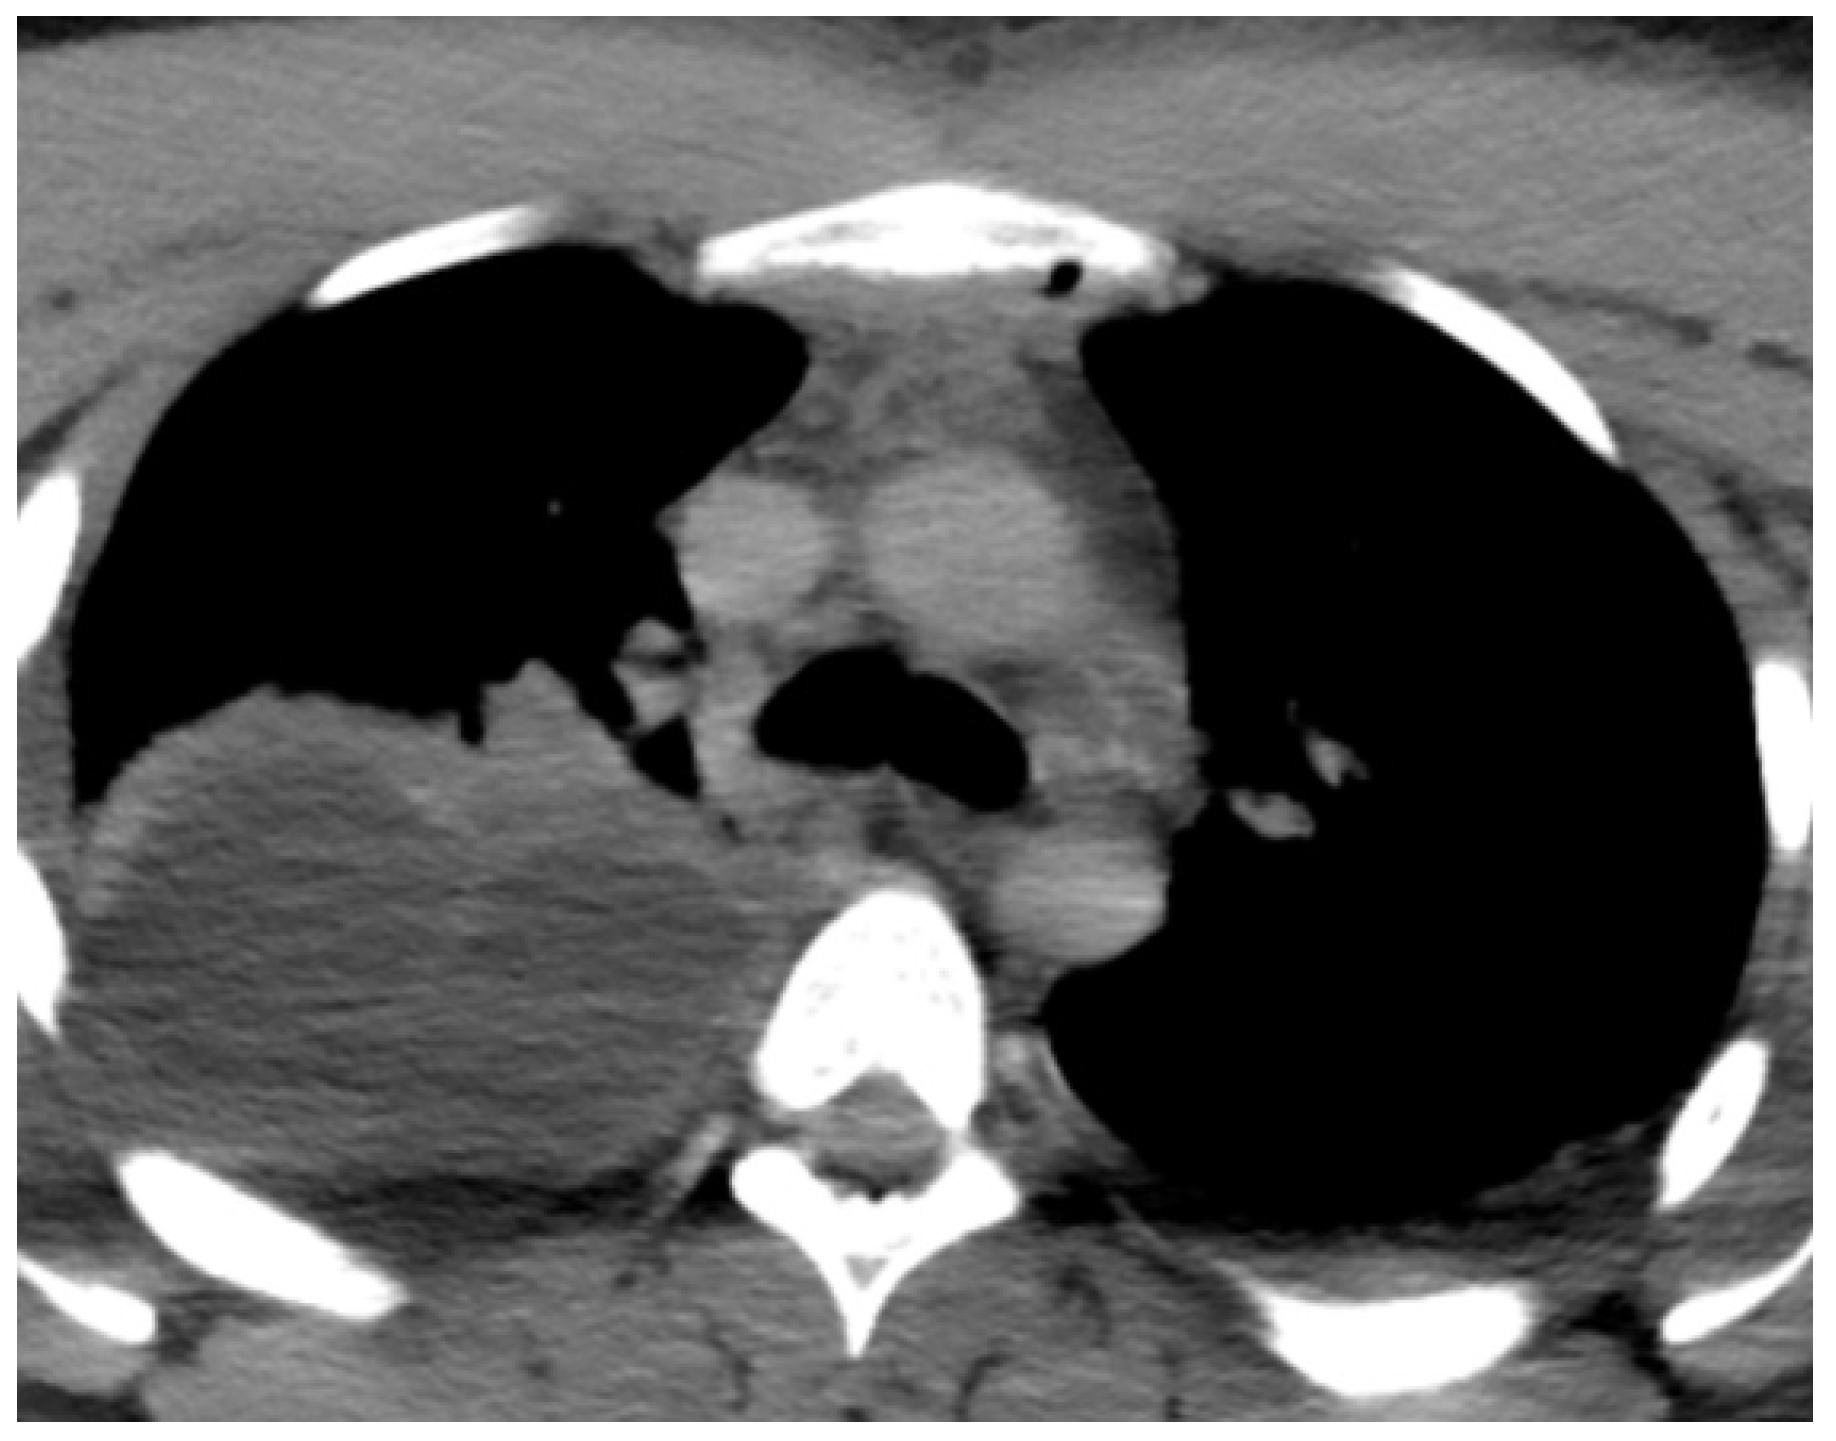

| Chest CT | pus collection: ventral from the thyroid gland measuring 68/14 mm, with a density of 34–40 HU reaching the carina | Purulent collection starting from the neck and reaching the anterior mediastinum above the carina, presence of gas collections | Multiple air collections involving all departments of the anterior mediastinum above the carina | Massive pneumomediastinum, presence of fluid-purulent collections in the anterior and posterior lower mediastinum below the carina |